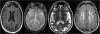

Methods/design: Cohort study in a randomly selected sample of 1000 participants, hypertensive aged 50 to 70 years old, with no history of previous stroke or dementia.On baseline all participants will undergo a brain MRI to determine the presence of brain infarcts and other cerebrovascular lesions (brain microbleeds, white matter changes and enlarged perivascular spaces) and will be also tested to determine other than brain organ damage (heart-left ventricular hypertrophy, kidney-urine albumin to creatinine ratio, vessels-pulse wave velocity, ankle brachial index), in order to establish the contribution of other subclinical conditions to the risk of further vascular events. Several sub-studies assessing the role of 24 hour ambulatory BP monitoring and plasma or genetic biomarkers will be performed.Follow-up will last for at least 3 years, to assess the rate of further stroke/transient ischemic attack, other cardiovascular events and cognitive decline, and their predictors.